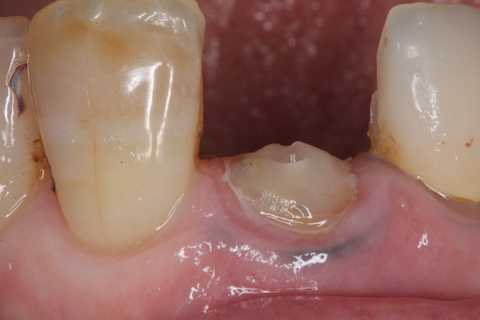

左下7遠心カリエスと8番抜歯 2025.07.29